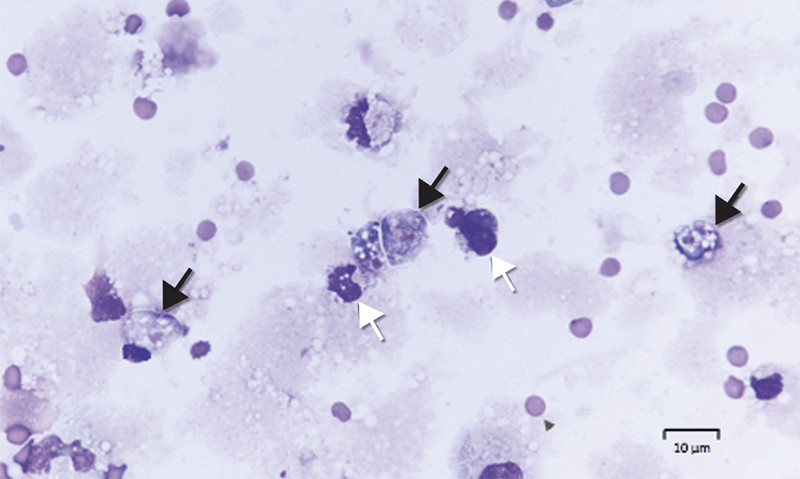

Diagnosis requires identification of motile trophozoites in CSF or characteristic morphology in stained specimens by a trained microbiologist (Box 1), with confirmation using molecular methods (PCR) or culture (Escherichia coli lawn culture). The trophozoites are visible in a wet unstained preparation of CSF (magnification, × 400), exhibiting sinusoidal movement by means of lobopodia; however, specimens need to be examined very soon after collection, as the amoebae degenerate rapidly in vitro and can be easily mistaken for leucocytes.

Box 1 – Microscopy of cerebrospinal fluid of Patient 2, showing trophozoites (Giemsa stain, black arrows) and mononuclear leucocytes (white arrows)